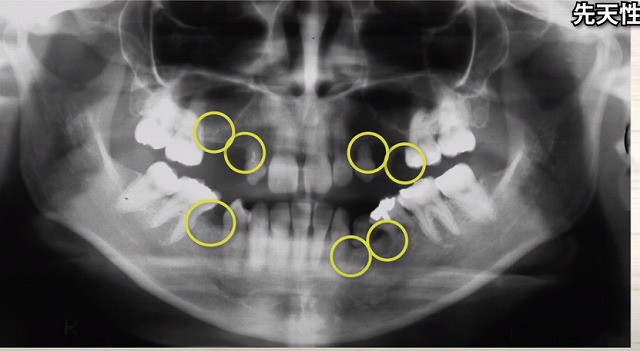

この方は

こんなにも歯が足りません。

歯の根っこの長さに注目すると

短い・短い子供の歯です。

後ろは大人の歯が生えてきました。

後ろから手前に大人の歯が倒れてくると

簡単に子供の歯は

埋まっている根っこが短いですから

簡単に押し倒されてしまいます

もともと大人の歯が生えていないから

ただ歯ブラシをしておいてくださいね

ということだけでは

防げないことがあります。